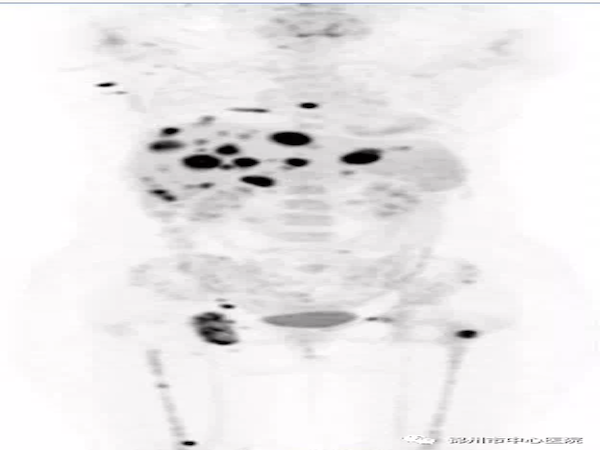

確診彌漫大B細胞淋巴瘤,臨床擬行化療,治療前行PET/CT基線評估提示為全身多發(fā)淋巴結累及,雙肺、左腎及腎周、骨骼多發(fā)累及;治療4個療程后行PET/CT治療中評估療效:除縱隔及左肺門淋巴結外,其余淋巴結、肺內(nèi)、左腎及骨骼病灶活性基本被抑制,提示臨床治療方案有效;臨床以原方案繼續(xù)治療4個療程,行PET/CT評估,縱隔及左肺門淋巴結消失,患者獲得臨床治愈。在該例患者的診治過程中,PET/CT明確告訴臨床,治療方案是否有效、患者的治療效果如何,讓患者承受最小的痛苦,花最少的錢得到最佳的治療效果。